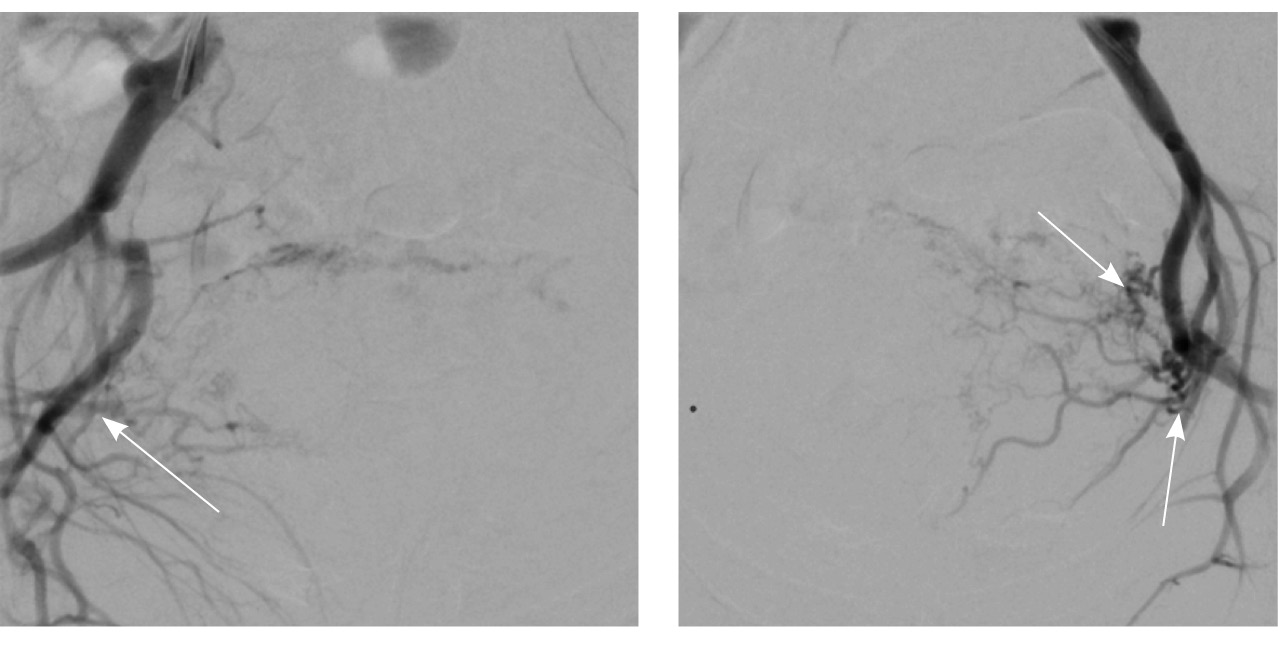

Исходя из клинической и визуальной картины, пациентке выполнено оперативное лечение. Первым этапом проведена эмболизация маточных артерий. Под местной анестезией раствором ропивакаина пунктирована правая лучевая артерия. Установлен интродьюсер 5F. Катетером НН последовательно катетеризированы левая и правая внутренние подвздошные артерии, выполнена ангиография. На ангиограммах: артериовенозная мальформация в проекции матки; афферентные артерии – маточные и цервиковагинальные – с обеих сторон, две ветви 1 мм в диаметре от левой внутренней подвздошной артерии; эфферентные сосуды – вены параметрия, внутренние подвздошные вены и яичниковые вены с обеих сторон (рис. 4).

Рис. 4. Данные рентгеноконтрастной ангиографии. А, Б – ангиограммы бассейнов правой и левой маточных артерий. Зоны патологической васкуляризации в проекции тела матки: массивная сеть измененных артерий и вен, ранний артериовенозный сброс в вены параметрия, внутренние подвздошные вены и яичниковые вены с обеих сторон. В, Г – ангиограммы бассейнов правой и левой цервиковагинальных артерий. Контрастирование зоны патологической васкуляризации в проекции шейки и нижнего отдела тела матки, ранний артериовенозный сброс в вены параметрия преимущественно слева и в левую внутреннюю подвздошную вену (стрелки)

Выполнена эмболизация маточных и цервиковагинальных артерий с обеих сторон материалом PVA (1000 мкм) и эмболами из гемостатической губки. На контрольных ангиограммах патологическое сосудистое сплетение не контрастируется, артериовенозный сброс устранен (рис. 5). Катетеры и интродьюсер удалены, выполнен компрессионный гемостаз, наложена асептическая давящая повязка. Контрастный препарат йодиксанол (320 мг йода/мл) – 300 мл. Эффективная доза – 1,8 мЗв.

Рис. 5. Контрольные снимки после эмболизации маточных и цервиковагинальных артерий. Ангиограммы бассейнов правой и левой внутренних подвздошных артерий. Правая маточная и цервиковагинальная артерии, а также патологическое сосудистое сплетение в их бассейне не контрастируются, ранний артериовенозный сброс устранен. Незначительное контрастирование сегмента патологической сети по единичной мелкой ветви внутренней подвздошной артерии справа, по двум мелким ветвям внутренней подвздошной артерии слева (указано стрелками)